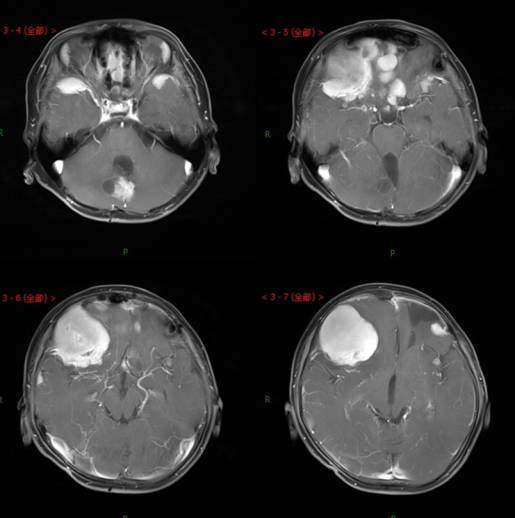

髓母细胞瘤由Bailey与Cushing于1925年首先报道,是好发于儿童的颅内恶性肿瘤,是中枢神经系统恶性程度最高的神经上皮性肿瘤之一有人认为其发生是由于原始髓样上皮未继续分化的结果。这种起源于胚胎残余细胞的肿瘤可发生在脑组织的任何部位,但绝大多数生长在第四脑室顶之上的小脑蚓部。